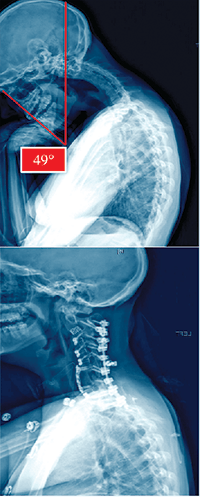

A 28-year-old female with a seven-year history of kyphoscoliosis and dystonia also presented with psoriatic arthritis, ankylosing spondylitis, and cervical dystonia. A three-hour anterior surgery was first performed followed by asymmetric osteotomies to correct the scoliosis at C3-4-5-6-7-T1, with anterior fusion from C2-T1. Posterior osteotomies were then performed in a more than five-hour surgery at all the same levels with a fusion from C2-T2.

The patient is now ambulating normally and expected to resume all normal activities better than she could preoperatively since her alignment is now nearly normal.